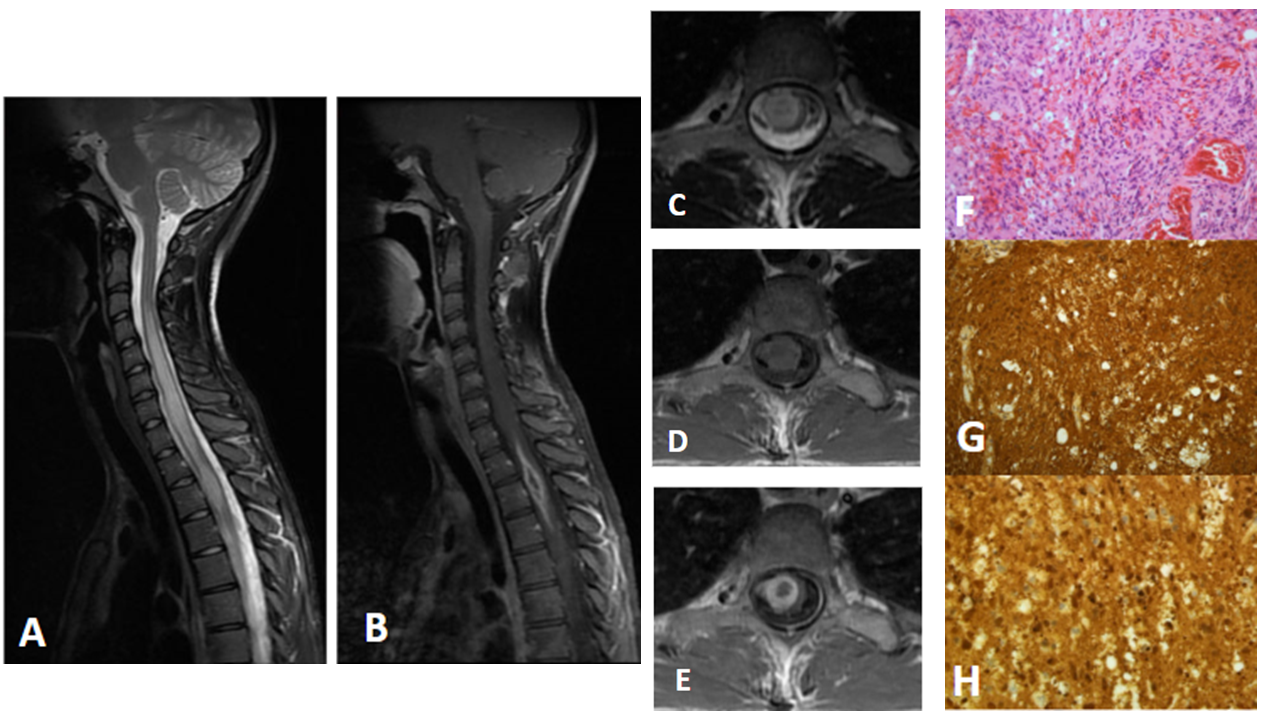

Figura A: RM de columna cervical potenciada en T2 en el plano sagital en la que se observa engrosamiento e hiperseñal T2 difusa del cordón medular desde C3-C4 hasta D6-D7.

Figura B: RM de columna cervical potenciada en T1 con gadolinio en el plano sagital en la que se observa lesión fusiforme con realce en anillo en los niveles D1-D3.

Figura C: RM de columna cervical potenciada en T2 en el plano axial en la que se observa lesión nodular intramedular a nivel de D3 que afecta principalmente la hemimédula derecha y asocia ensanchamiento del cordón medular. Es heterogénea con centro hipointenso y periferia hiperintensa.

Figura D: RM de columna cervical potenciada en T1 en el plano axial en la que se observa como la lesión es isointensa con la médula.

Figura E: RM de columna cervical potenciada en T1 con gadolinio en el plano axial en la que se observa un realce en anillo grueso tras la administración de contraste.

Figura F: Proliferación tumoral glial ricamente vascularizada y heterogénea constituida por células atípicas y pleomórficas con núcleos irregulares y algunos hipercromáticos, vesiculosos con cromatina gruesa dispersa y ocasionales nucléolos, con áreas de morfología epitelioide, fusocelulares, multinucleadas y otras de aspecto histiocitario, acompañada de algunos polimorfonucleares, cuerpos apoptóticos y restos nucleares con ocasionales mitosis. Se observa proliferación endotelial y focos de necrosis.

Figuras G y H: tumoración con técnicas de inmunohistoquímica positiva para PGFA y S100, respectivamente, siendo característico de tumores gliales.